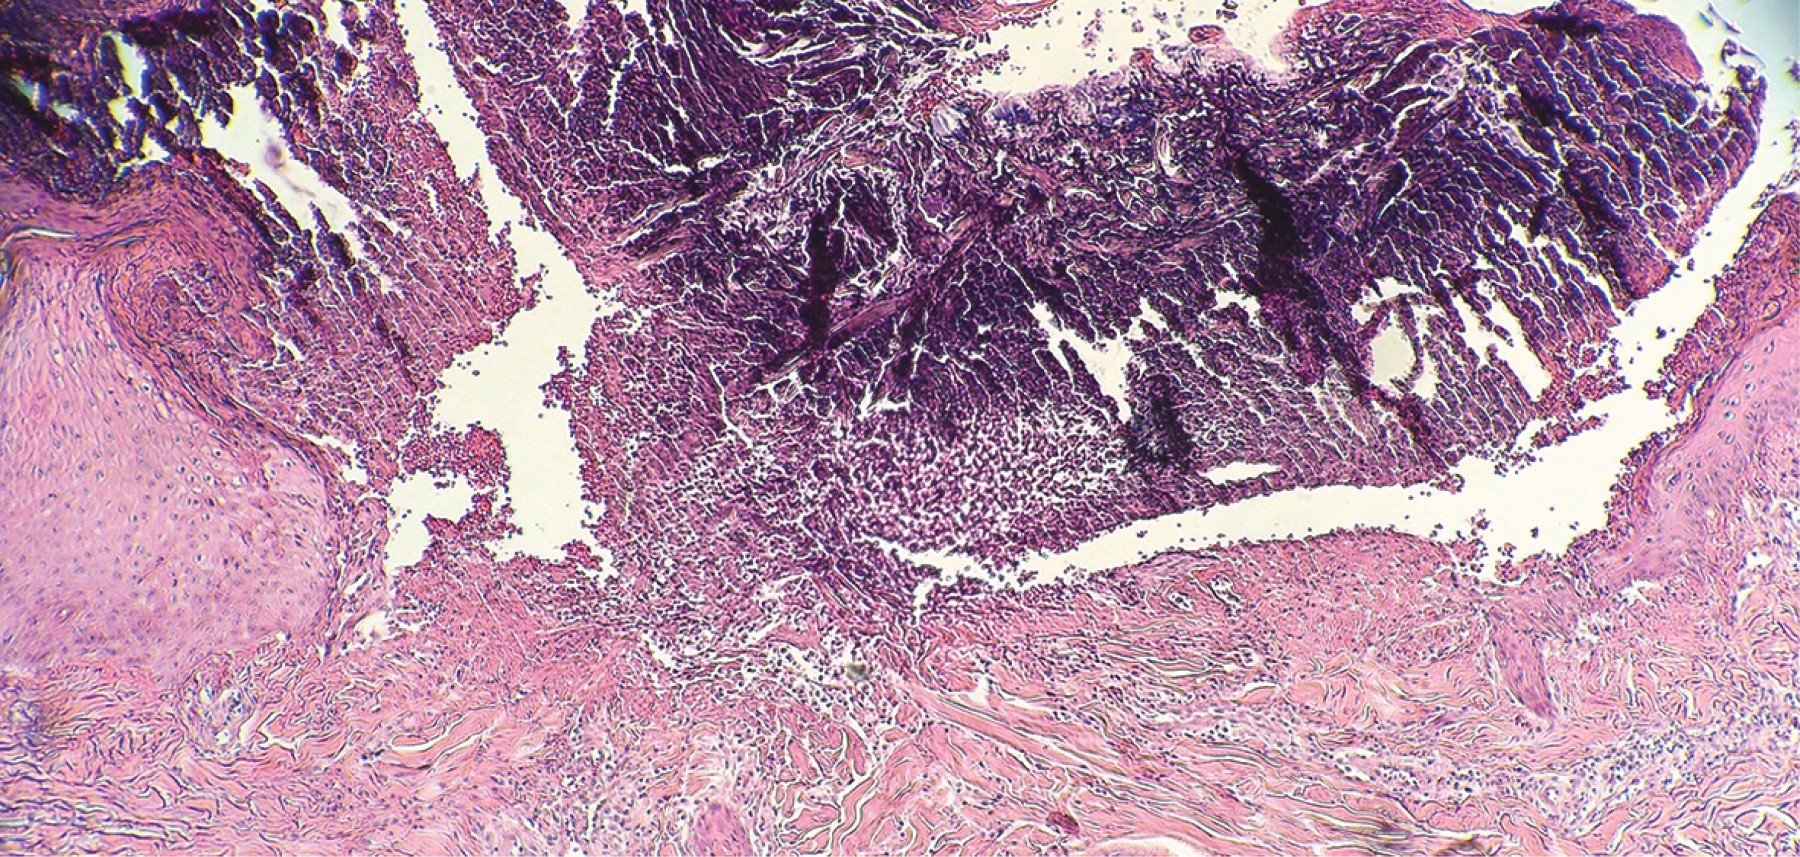

Acquired reactive perforating collagenosis

Perforating dermatoses are a group of diseases clinically characterized by transepidermal shedding of various skin materials. Four primary classical forms have been described in which the removal material represents the distinctive clinical picture. In secondary cases, the perforation and elimination of the fibers of the connective tissue constitute a phenomenon that accompanies other dermatoses. Acquired reactive perforating collagenosis belongs to the latter group. The etiology is not clear. It is associated with metabolic disorders and certain neoplasms. Pruritus is considered a key pathogenic factor, since constant scratching generates microtrauma in genetically predisposed patients, causing focal degeneration of collagen fibers. The most frequent topography is in the trunk (77%) and the extremities (64%), of which the extensor areas are involved. It manifests clinically with the presence of erythematous papules with an umbilicus appearance, with a firmly adhered keratin plug in the center. Histopathology shows transepidermal removal of collagen fibers. Because the treatment is not yet well standardized, the management of pruritus is considered one of the bases of it. It is recommended to treat the associated diseases.

Figure 2